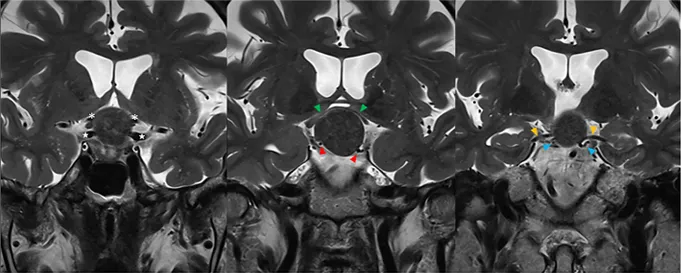

具体分析:MRI显示一个球形病变占据垂体漏斗后部及鞍上间隙,且肿瘤与垂体柄和正常垂体组织紧密相邻(黄色箭头)。

视交叉(绿色箭头)和动眼神经(蓝色箭头)由于受到肿瘤挤压而产生移位,视交叉已经变薄。此外,肿瘤与颈动脉(白色星号)、后交通动脉(红色箭头)、大脑前动脉(白色星号)和大脑后动脉(黄色箭头)紧密粘连,术中剥离困难,存在较大的出血风险。

要求:手术必须要在保留垂体及其功能的基础上进行安全切除,同时不损伤周围重要神经血管,谨慎将肿瘤与其剥离开来。